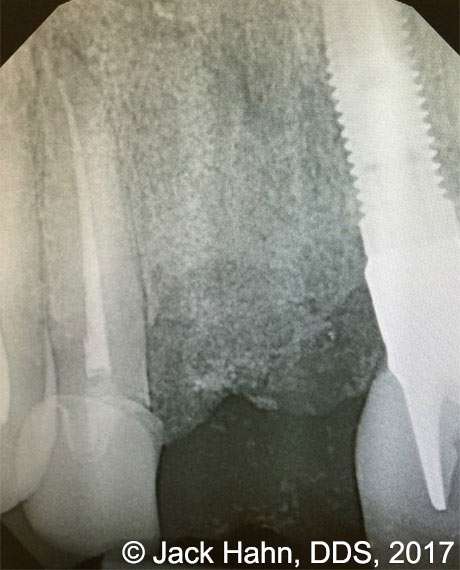

CASE #9 Removal of Failed Dental Implant

Jack Hahn, DDS, removed a failed Bicon implant. The labial plate was absent and the surrounding soft tissue was inflamed and suppurating. All remnants of soft and fibrotic tissue were removed using a LightScalpel CO2 laser. The site was then grafted with Newport Biologics mineralized cancellous cortical particular material and covered with Newport Biologics putty. After 6 months of healing and new bone formation, Dr. Hahn will place a new implant in #8 area.